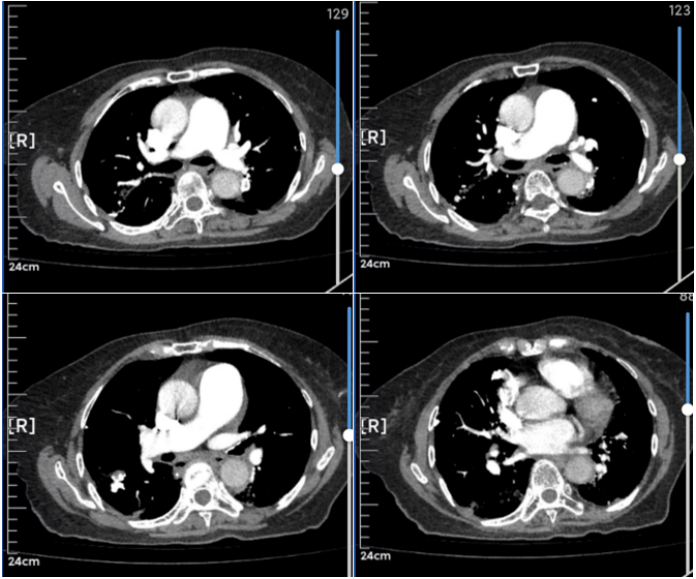

完善CTPA检查

入院后完善CTPA检查:肺动脉稍增宽,所示肺动脉及主要分支未见确切充盈缺损;慢支-肺气肿改变,两肺多发肺大疱及炎症改变,两肺多发结节、斑结及钙化灶,多为陈旧性病变,双侧腋窝及纵隔多发淋巴结,两侧胸膜增厚,主动脉壁部分钙化,心影增大,心包少量积液(图3)

图片

图3  患者CTPA检查结果